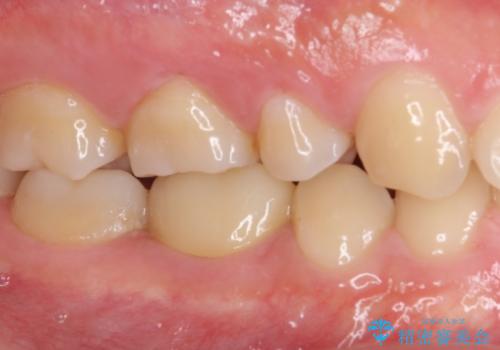

神経近くにまで及んだ大きなむし歯のセラミッククラウン

虫歯除去後に痛みは収まり、神経も保存することができました。

変色していた歯もセラミッククラウンで自然な色合いとなり、患者様には大変満足していただきました。